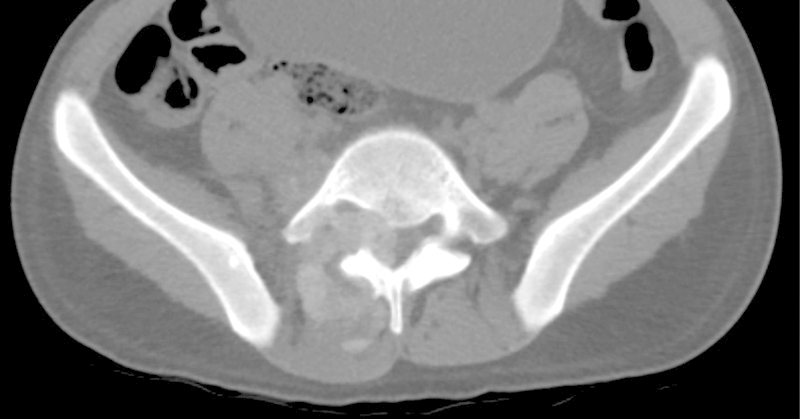

研究设计案例报告。目的:本研究的目的是报道腰椎骨痛风的发生。方法通过一个病例报告来说明脊柱痛风的要点,我们简要回顾了痛风的文献,因为它与骨科和脊柱表现以及管理指南有关。结果:本病例报告详细描述了一名24岁男性腰椎痛风病史和3年进行性背痛的重大临床发现。结论高怀疑指数有助于腰痛或有痛风病史的神经系统疾病的诊断。既往痛风史(尤其是痛风石)、高尿酸血症和影像学特征有助于临床医生诊断脊柱性痛风。早期诊断有可能避免手术干预的需要。

Study Design Case report. Objective The objective of this study is to report the occurrence of tophaceous gout in the lumbar spine. Methods Using a case report to illustrate the key points of gout in the spine, we provide a brief review of gout in the literature as it relates to its orthopedic and spinal manifestations as well as guidelines for management. Results This case report details the occurrence of a large and clinically significant finding of tophaceous gout in the lumbar spine in a 24-year-old man with a known history of gout and a 3-year history of progressive back pain. Conclusion A high index of suspicion can assist in diagnosis of patients presenting with back pain or neurologic findings with a history of gout. A previous history of gout (especially the presence of tophi), hyperuricemia, and the radiological characteristics presented here should aid the clinician in making the diagnosis of spinal gout. Early diagnosis has the potential to prevent the need for surgical intervention.